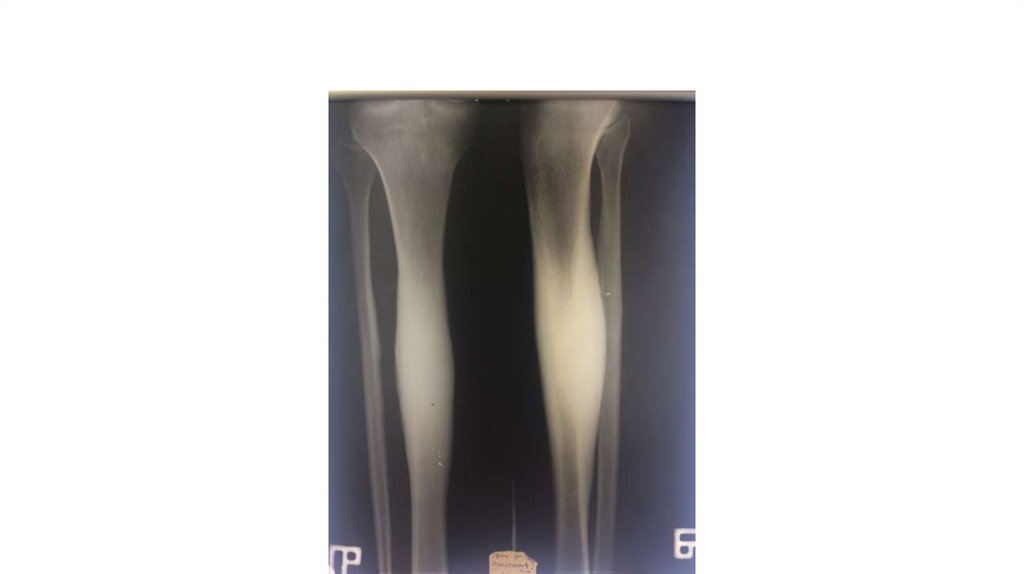

Воспалительные заболевания опорнодвигательного аппарата

«Воспалительные

заболевания опорнодвигательного аппарата»